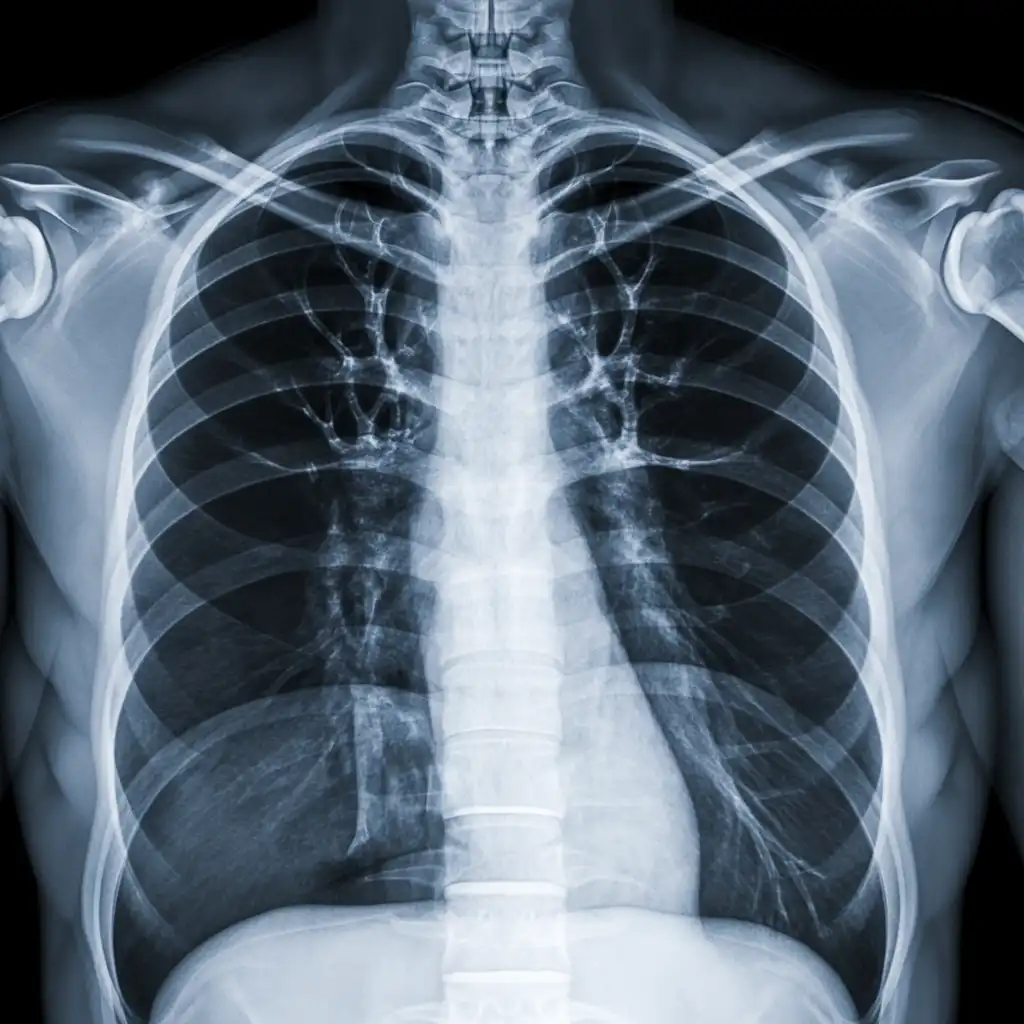

Il professionista entra con apparecchiature a basso dosaggio e schermi protettivi: bastano 2 × 2 m di spazio vicino al letto o alla poltrona. In pochi minuti acquisisce immagini HD, proprio come in un reparto ospedaliero.

Le immagini (formato DICOM) vengono caricate su un server crittografato e inviate immediatamente al radiologo. Se servono scatti aggiuntivi, il tecnico resta in collegamento video per eseguirli al volo.

Il medico radiologo analizza le immagini e firma il referto digitale all’istante. Ricevi il referto cartaceo e le immagini su chiavetta USB consegnati direttamente a casa tua subito dopo l'esame.

Usiamo le stesse apparecchiature certificate CE dei reparti ospedalieri, calibrate regolarmente. I referti sono validi per visite specialistiche, pronto soccorso e pratiche assicurative, e restano archiviati per 10 anni per ogni esigenza futura.